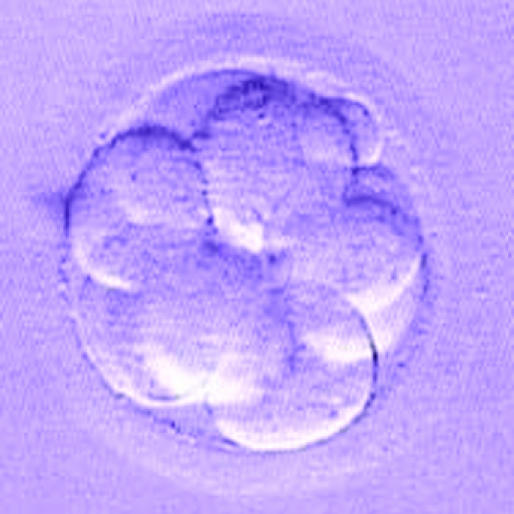

Figure 7.

The top photographs from left to right show human embryos in vitro at the 2-cell stage (day 1); 4-cell stage (day 2); and 8-cell stage (day 3). The bottom row shows a compacted morula (day 4); a blastocyst (day 5); and a hatching blastocyst (day 6)